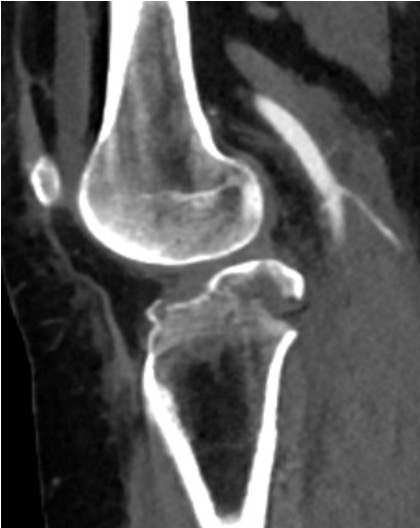

CT demonstrating medial tibial plateau in setting of knee dislocation and posterolateral corner injury